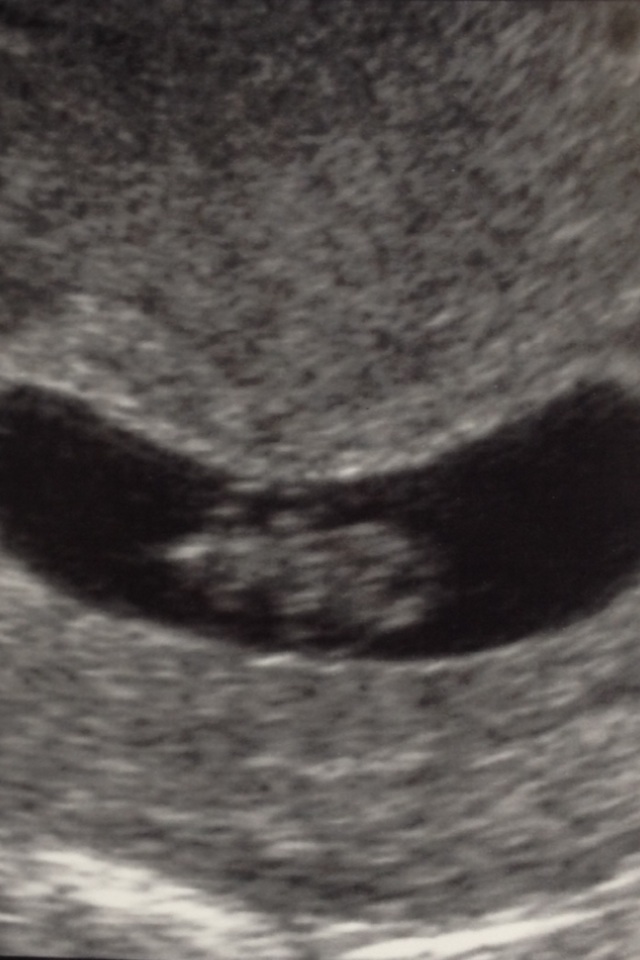

I love u/s pics!! Here is mine from last week @ 8w2d. 167 heartbeat. The tech labeled him/her baby, as you can see...... just in case I wasn't sure what I was looking at! :>

It was such a relief to hear that little heart beating!!